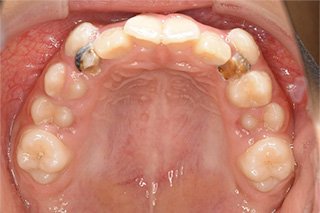

顎顔面矯正症例 11歳女児 Case

| 主訴 | 永久歯が変な所からはえてきている|顔貌 | |

|---|---|---|

| 施術内容 | 矯正1期治療 | |

| 治癒期間 | 1年5ヶ月間 | |

| 費用 | 459,200円(税込) | |

| リスク・ 副作用 | 痛みを伴う | |